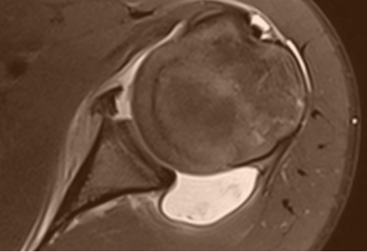

• Mr av skulder

MSK-fellowship mars 2022 - Roar Pedersen